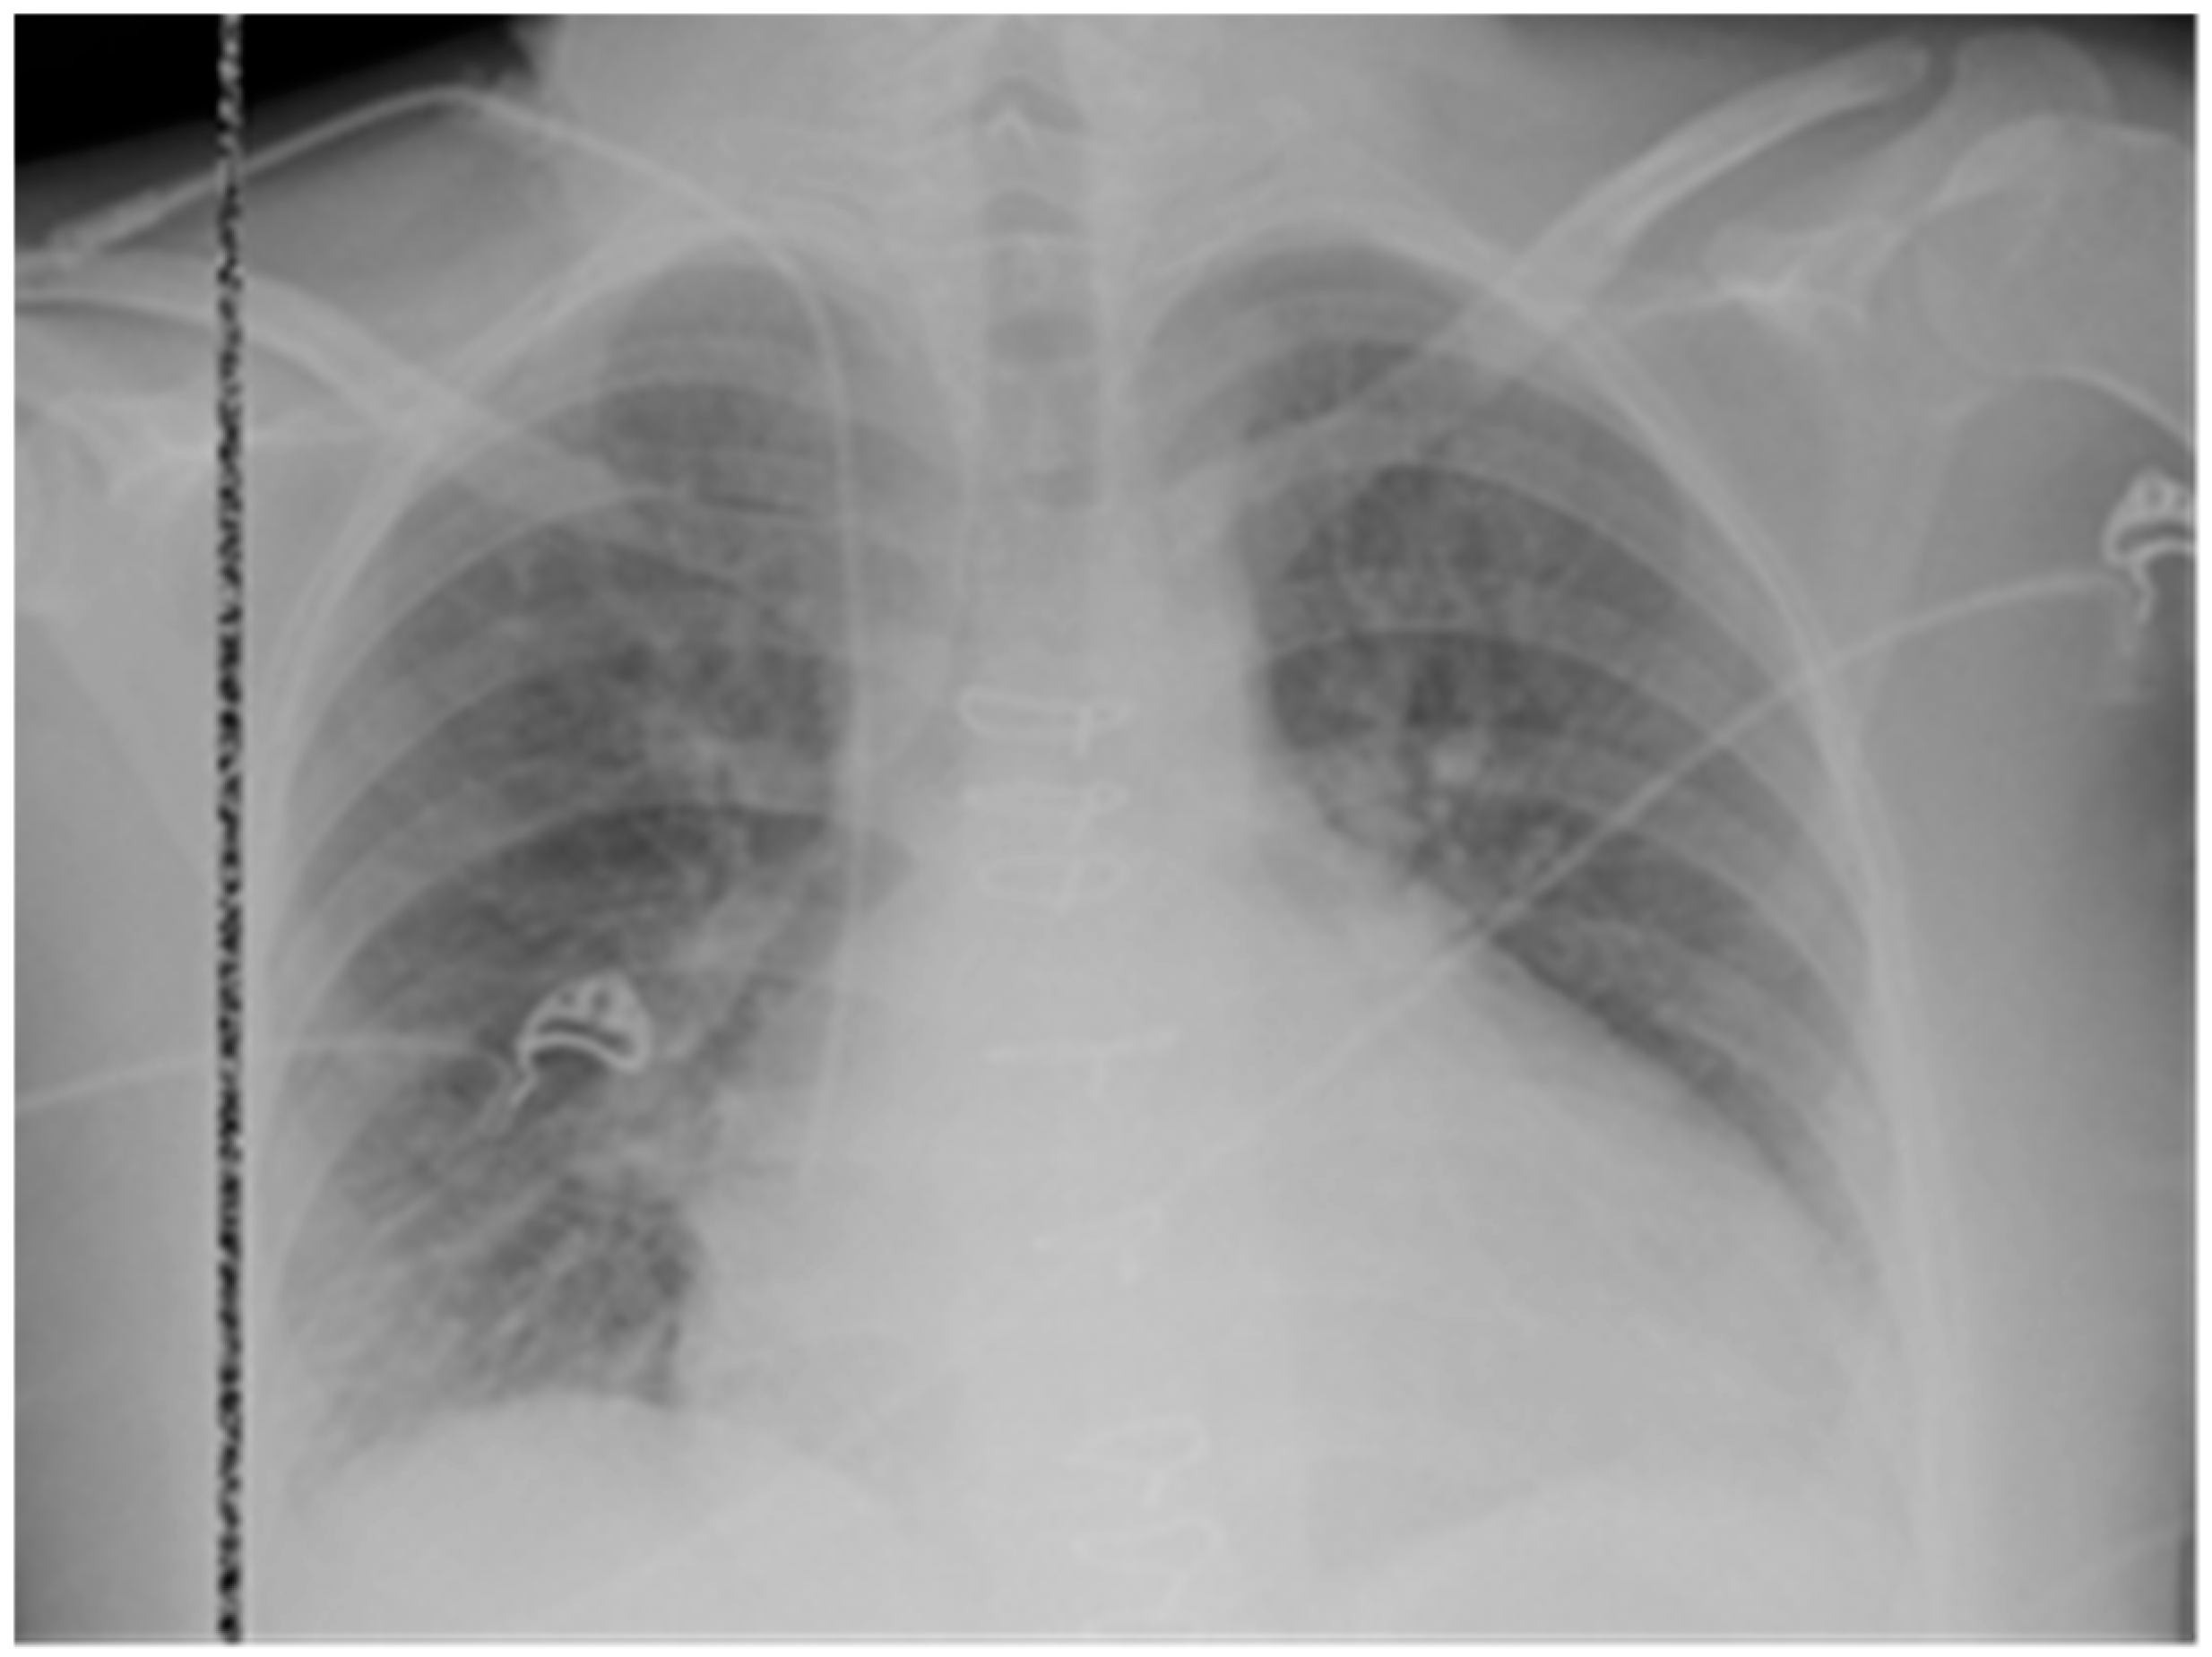

The patient underwent emergency endomyocardial biopsy (EMB) and coronary angiography (CAG) due to suspected cardiac allograft rejection. CAG results (Figure 2) revealed development of CAV: the anterior interventricular artery was diffusely altered throughout its entire length with stenosis of up to 70% in the middle and distal segments. The circumflex artery was diffusely altered with stenosis of up to 30% in the middle third. The marginal artery was without significant stenosis, the periphery was satisfactory. The right coronary artery was diffusely altered throughout its entire length, with stenosis in the middle and distal segments of up to 50%.

A total of eight ECP sessions were performed, two sessions for 2 days with a 7-day break. No complications were recorded. Significant positive dynamics were achieved in the form of a decrease in the anti-HLA class II titer to 2000 MFI; DSA were absent. Based on the TTE results, LVEF: 56%, EDV: 85 mL, and TAPSE: 12 mm. Control CAG recorded improved blood flow in all coronary arteries, no hemodynamically significant stenoses were detected (Figure 2). After treatment was completed, the other EMB was performed with positive histological results: stromal edema persists but there was no CAV; there were no macrophages in the vascular lumen but there were still signs of AMR2 (Figure 3). The level of NT-proBNP decreased to 2268 pg/mL, and troponin to 0.007 ng/mL.

Figure 2. Coronary angiography (CAG) data. (AC)—initial results prior to initiation of immunosuppressive treatment. (A) Selective coronary angiography of the left coronary artery (LCA) in the right caudal projection: the left coronary artery trunk and circumflex artery (CA) are visualized, diffusely changed with stenosis of up to 30%, with marginal arteries extending from it; the anterior interventricular artery (AIVA) with stenosis of up to 70% in the middle and distal thirds, with diagonal arteries extending from it. (B) Selective coronary angiography of the LCA in the standard caudal projection, where the AIVA and CA with branches extending from them are also visualized. (C) Selective coronary angiography of the right coronary artery (RCA) with stenosis in the middle and distal third up to 50% in the left caudal projection with its branches, pronounced depletion of the distal bed. (DF)—CAG results in 2 weeks after AMR3 was verified and immunosuppressive treatment was initiated. (D) Selective coronary angiography of the LCA in the right caudal projection: LCA trunk, OA, LAA, without hemodynamically significant stenosis against the background of rejection treatment. (E) Selective coronary angiography of the LCA in the standard caudal projection. LAA, OA without hemodynamically significant stenosis, increased blood supply to the distal bed, branches of LAA and OA. (F) Selective coronary angiography of the right coronary artery (RCA), without hemodynamically significant stenosis, with improved blood supply to the distal bed. Dynamic increase in arterial lumen diameter (in (D) vs. (A)). Visualization of small-diameter arteries has been added (in (E) vs. (B)). Increase in RCA lumen diameter and visualization of arterial diameter ((F) vs. (C)).